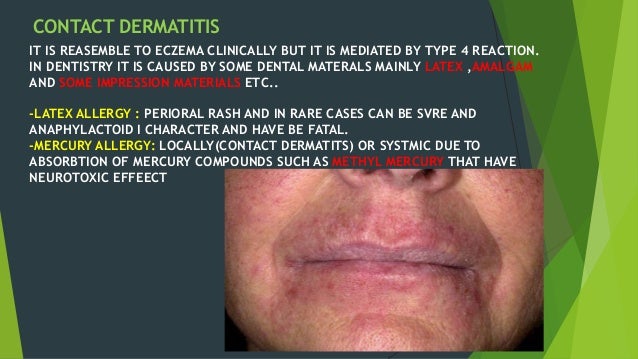

Allergy And Autoimmune Diseases In Dentistry

www.slideshare.net

www.slideshare.net

allergy dentistry autoimmune diseases dermatitis